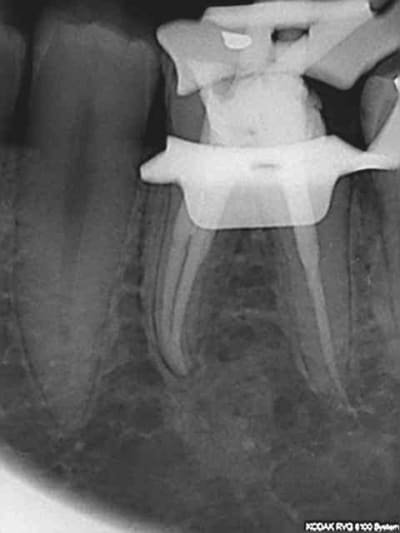

60 mn environ pour ces 2 là, le canal mv2 augmente le temps d'exéctution de 15 à 30 mn surtout si l'entrée est proche du mv1. Il n'y a pas photo entre la préparation canalaire du r25 VS f2 protaper.

Comme les protapers, ca remplace le s2,f1 f2 et ça casse pas. Recherche des canaux avec le sx sur entran , ouverture largo n°3, re sx pour progresser apicalement, s1 sur endomaster pour lt, r25 sur wd silver et terminé (si le s1 ne va pas direct à l'apex un coup de r25 peut s'avérer nécessaire pour les canaux longs et courbes comme sur la 16 ci-dessus ou la lt était à 25 mm)